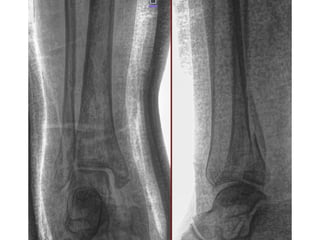

NOMBRE:MARTINEZ SANCHEZ IVAN

NSS:3906871557 1M1987OR

URGENCIAS A

Edad: 32 AÑOS

Comorbilidades: NINGUNA

Fecha de la lesión: 13/09/25

Mecanismo de lesión: ACCIDENTE EN MOTOCICLETA

Laboratorios: DENTRO DE NORMALIDAD

Valoraciones: NA

Diagnósticos: FRACTURA DIAFISIARIA TERCIO MEDIO DE TIBIA DERECHA EXPUESTA GA II AO 42A1C

Cirugía Proyectada: ASEO QUIRURGICO+ DESBRIDAMIENTO + REDUCCION CERRADA VS ABIERTA CON FIJACION INTERNA CON

COLOCACION DE FIJADORES EXTERNOS VS DCP 4.5 MM A TIBIA DERECHA

Material OSS Solicitado: NA

NOMBRE:MARTINEZ SANCHEZ IVAN NSS:39068715571M1987OR URGENCIAS A Edad: 32 AÑOS Comorbilidades: NINGUNA Fecha de la lesión: 13/09/25 Mecanismo de lesión: ACCIDENTE EN MOTOCICLETA Laboratorios: DENTRO DE NORMALIDAD Valoraciones: NA Diagnósticos: FRACTURA DIAFISIARIA TERCIO MEDIO DE TIBIA DERECHA EXPUESTA GA II AO 42A1C Cirugía Proyectada: ASEO QUIRURGICO+ DESBRIDAMIENTO + REDUCCION CERRADA VS ABIERTA CON FIJACION INTERNA CON COLOCACION DE FIJADORES EXTERNOS VS DCP 4.5 MM A TIBIA DERECHA Material OSS Solicitado: NA